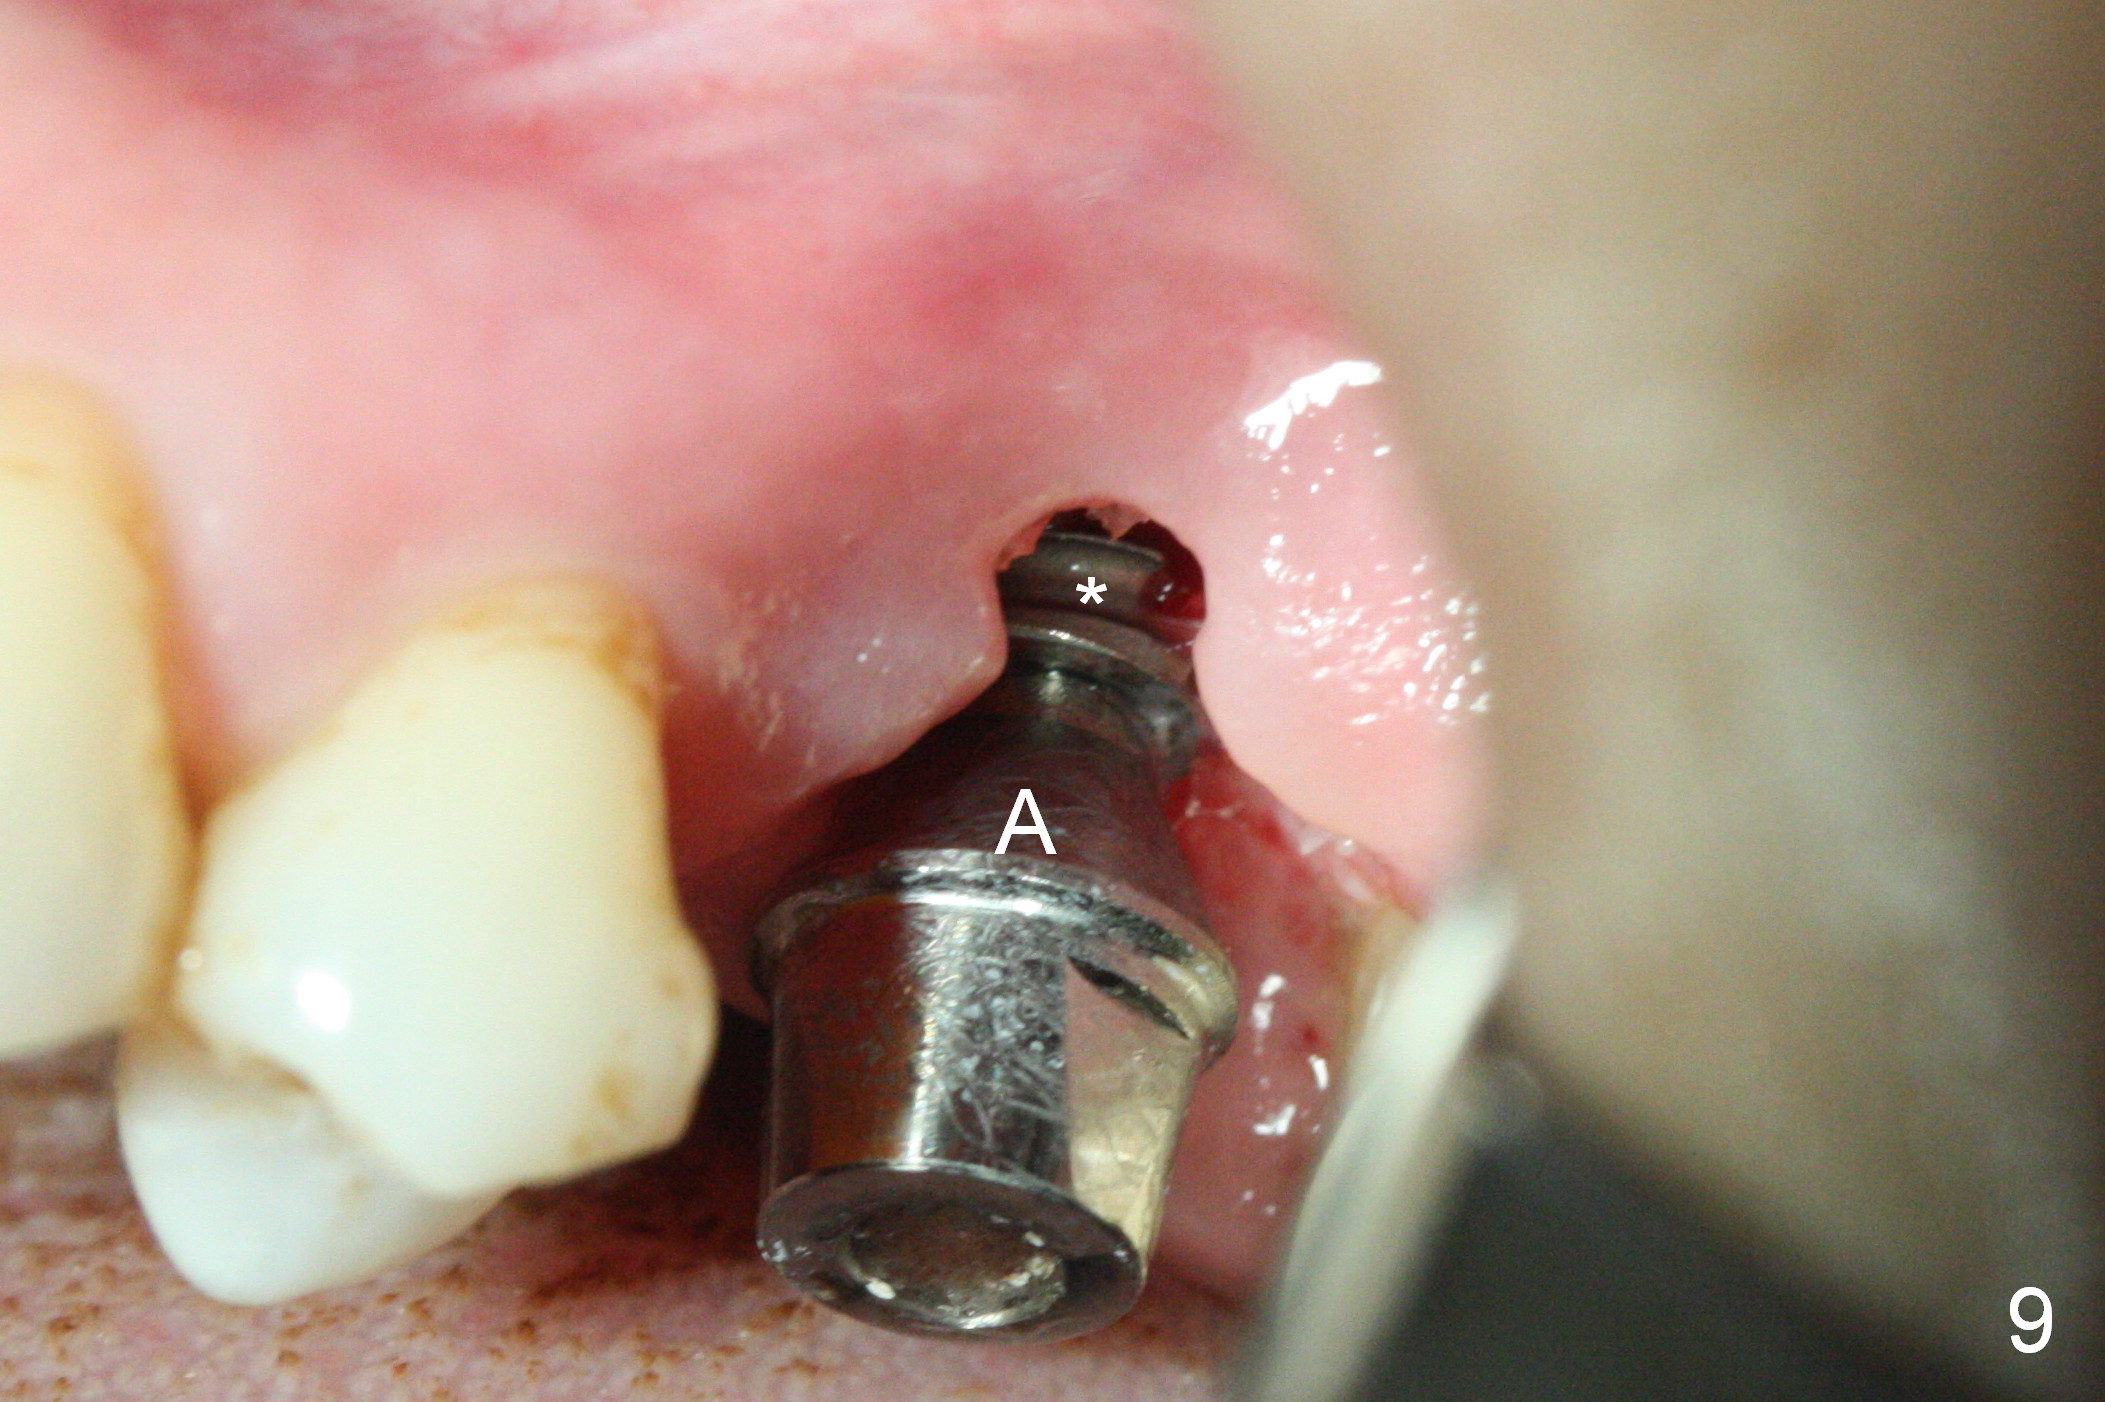

There is abundant subgingival calculus on the surfaces of the extracted tooth at #14 (Fig.1: P: palatal; MB: mesiobuccal), corresponding to the large empty socket (Fig.2 without septal bone, the buccal plate being low). Osteotomy is established palatally with Magic Expander (ME) 3.0 mm for ~ 3 mm deep (Fig.3,4) with minimal stability so that it moves during X-ray taking (Fig.4). Since the bone is dense, Magic drill 4.3 mm is used after application of ME 3.8 and 4.3 mm to complete sinus lift (Fig.5 (panoramic X-ray)). A 5x11 mm implant is placed with ~ 30 Ncm, followed by insertion of 6.5x4(3) mm Hexa abutment, bone graft and collagen membrane (Fig.6). The latter is kept in placed with an immediate provisional with clearance from the opposing dentition (Fig.7 *). Between the 1st and 3rd weeks postop, the buccal gingiva recedes with loss of bone graft (Fig.8 <) and implant thread exposure (Fig.9 * (A: abutment)). After inducing hemorrhage, allograft is placed (Fig.10 >), followed by collagen dressing (Fig.11 >). The wound closes by adding new acrylic (Fig.12 *). Thirteen days later, food is trapped in the buccal gap (Fig.13 ^). It appears that the provisional does not help wound healing. The provisional and abutment are removed; incorporating bone graft (Fig.14 *) and the implant are exposed. After placing collagen plug against the bone graft and implant, the wound is closed by periodontal dressing.